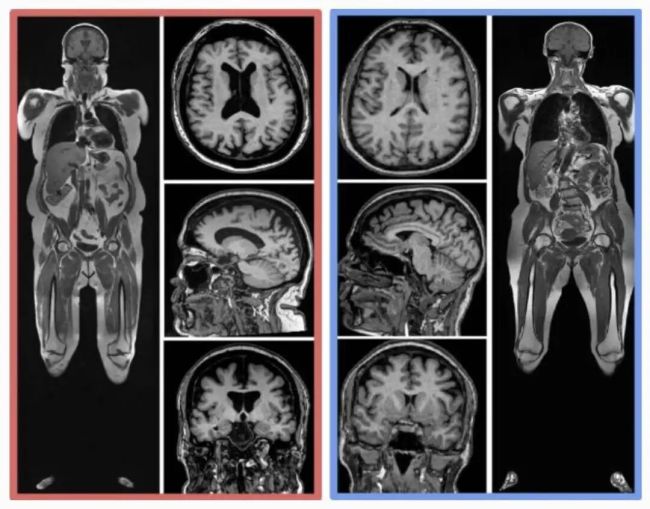

同样年龄的人,腹部脂肪(皮下和内脏)更多,脑部图像显示出更小的脑容量。

左侧红色受试者,四肢和腹部有更多的脂肪(亮色区域),大脑更多黑色空间。

图片来源:参考文献 [1]